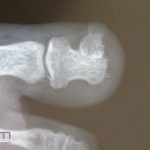

Diagnóstico:

Clínico, radiografia.

RX: proliferação óssea subungueal.